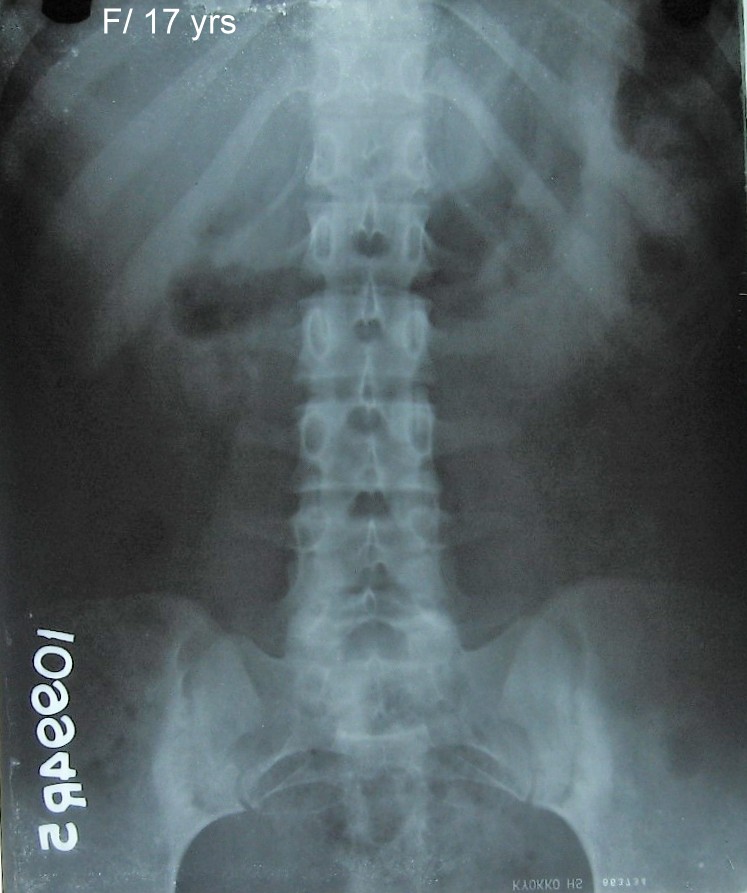

Lumbar Spine A.P of a a 17 year old female